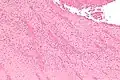

Low magnification micrograph showing laminations in a thrombus in a fatal pulmonary embolism. H&E stain. -